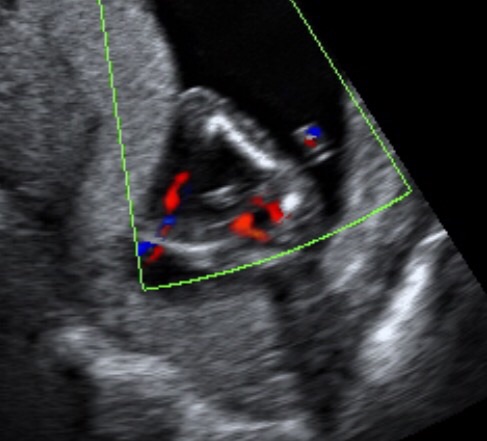

My tech guesses boy but said not to go buy anything just yet of course. I will know for sure at 19-20 weeks as private centres here won't check until 18 weeks, might as well wait a week or two for my anatomy scan.

The photos aren't the best, but guesses are welcome!